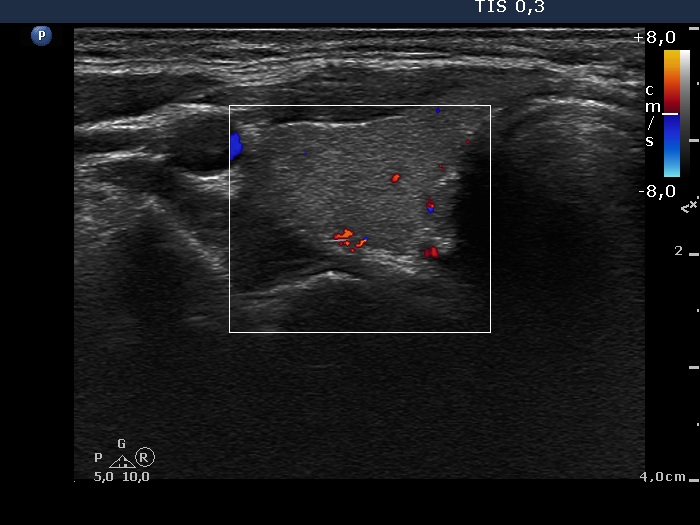

First examination (1st row of images)

Clinical data: A 29-year-old woman requested a second opinion. She was treated for Graves' disease for 2 months. The TSAb was initially 8.9 U/L, the FT4 was 54.2 pM/l. She get 30 mg methimazole therapy. Her complaints have already decreased.

Palpation: no abnormality.

Results of blood test: hyperthyroidism - TSH undetectable, FT4 29.2 pM/L, FT3 8.91 pM/L.

Ultrasonography: The thyroid was minimally enlarged and moderately hypoechogenic. The vascularization was a bit increased.

The dose of methimazole was reduced to daily 15 mg.